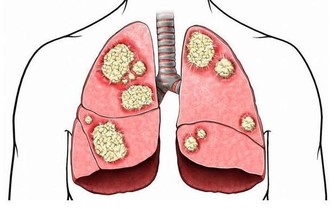

雖然說生命在於運動,經常鍛煉有助於補充陽氣,但是事猶不及,過度運動卻不是件好事。對於本身氣血虧虛的人來說,運動強度過大會導致排汗過多,這樣就會造成肺氣不足,陽氣大量損耗,所以運動一定要講究適度,否則只能適得其反。